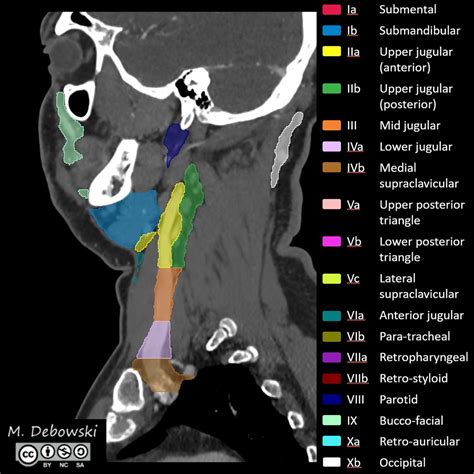

The neck is divided into several levels to facilitate the identification and classification of lymph nodes. This systematic approach is essential for accurate diagnosis and treatment planning. The neck lymph node levels are typically categorized into seven levels, each with specific anatomical boundaries and clinical significance.

Level I lymph nodes are located in the submental and submandibular regions. The submental nodes are found beneath the chin, while the submandibular nodes are situated below the lower jaw. These nodes drain lymph from the floor of the mouth, the tip of the tongue, and the lower lip. They are crucial for detecting infections or malignancies in these areas.

Level II lymph nodes are located along the upper third of the internal jugular vein. These nodes drain lymph from the nasopharynx, oropharynx, and the upper part of the larynx. They are important for evaluating conditions such as tonsillitis, pharyngitis, and cancers of the head and neck.

Level III lymph nodes are situated along the middle third of the internal jugular vein. These nodes receive lymph from the oral cavity, oropharynx, and larynx. They are often involved in the spread of malignancies from these regions and are critical for staging head and neck cancers.

Level IV lymph nodes are found along the lower third of the internal jugular vein. These nodes drain lymph from the larynx, thyroid gland, and lower part of the pharynx. They are significant in the evaluation of thyroid cancers and other malignancies in the lower neck region.

Level V lymph nodes are located in the posterior triangle of the neck, bounded by the sternocleidomastoid muscle, trapezius muscle, and clavicle. These nodes drain lymph from the scalp, posterior neck, and upper back. They are important for detecting infections and malignancies in these areas.

Level VI lymph nodes are situated in the anterior compartment of the neck, between the hyoid bone and the suprasternal notch. These nodes drain lymph from the thyroid gland, larynx, and central compartment of the neck. They are crucial for evaluating thyroid cancers and other malignancies in the anterior neck region.

Level VII lymph nodes are located in the superior mediastinum, below the suprasternal notch. These nodes drain lymph from the thyroid gland, larynx, and trachea. They are important for detecting malignancies that have spread from the neck to the mediastinum.